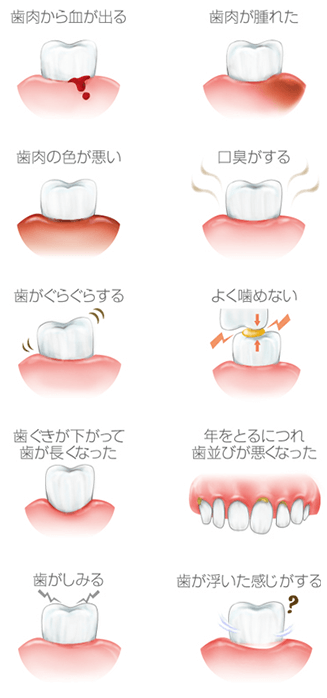

歯周病は歯肉炎・歯周炎の総称で、気づかぬうちに進行していき、成人の8割が罹っているといわれています。

最悪の場合歯が抜け落ちてしまう恐れがあり、日本人の歯を失う原因第一位の病気です。

また、口腔内だけではなく、全身疾患へ繋がるリスクもございますので、少しでも気になることがあれば、早めの受診をおすすめいたします。

下記に当てはまる症状がある方は、歯周病の可能性がございます。

歯周病は、歯垢(プラーク)という細菌の塊が歯と歯ぐきの間の歯周ポケットに溜まり、細菌が繁殖することによって引き起こされます。歯垢は放置すると石灰化して歯石となり、日々の歯みがきでは除去できなくなる上、歯周ポケットを深くする原因となり、歯周病を進行させてしまいます。